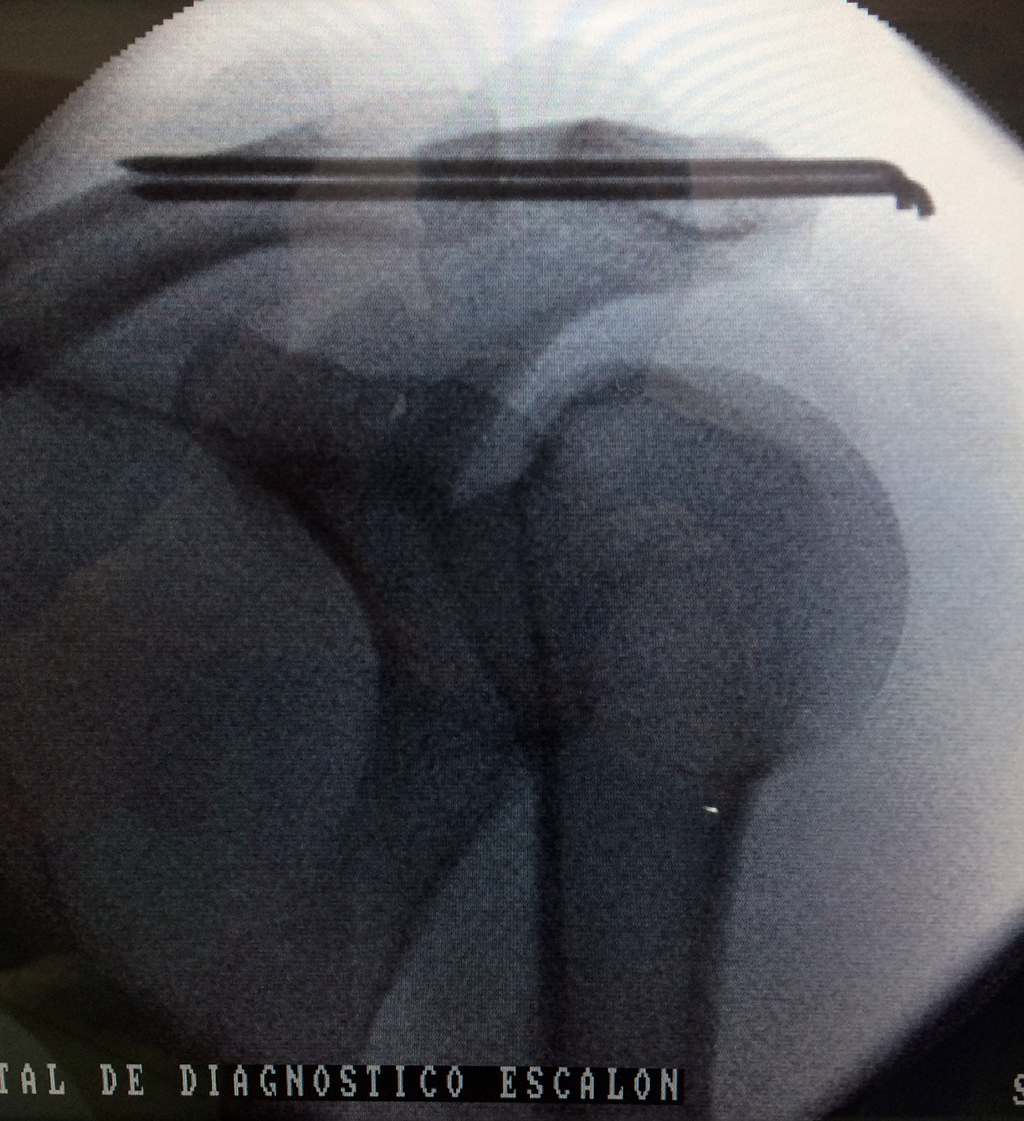

Cirugías de Calcaneo - Clavícula

La clavícula es un hueso largo, con forma de "S" itálica, situado en la parte anterosuperior del tórax. Junto con la escápula forman la cintura escapular. Se puede palpar por toda su longitud y se extiende del esternón al acromion de la escápula, siguiendo una dirección oblicua lateral y posterior.